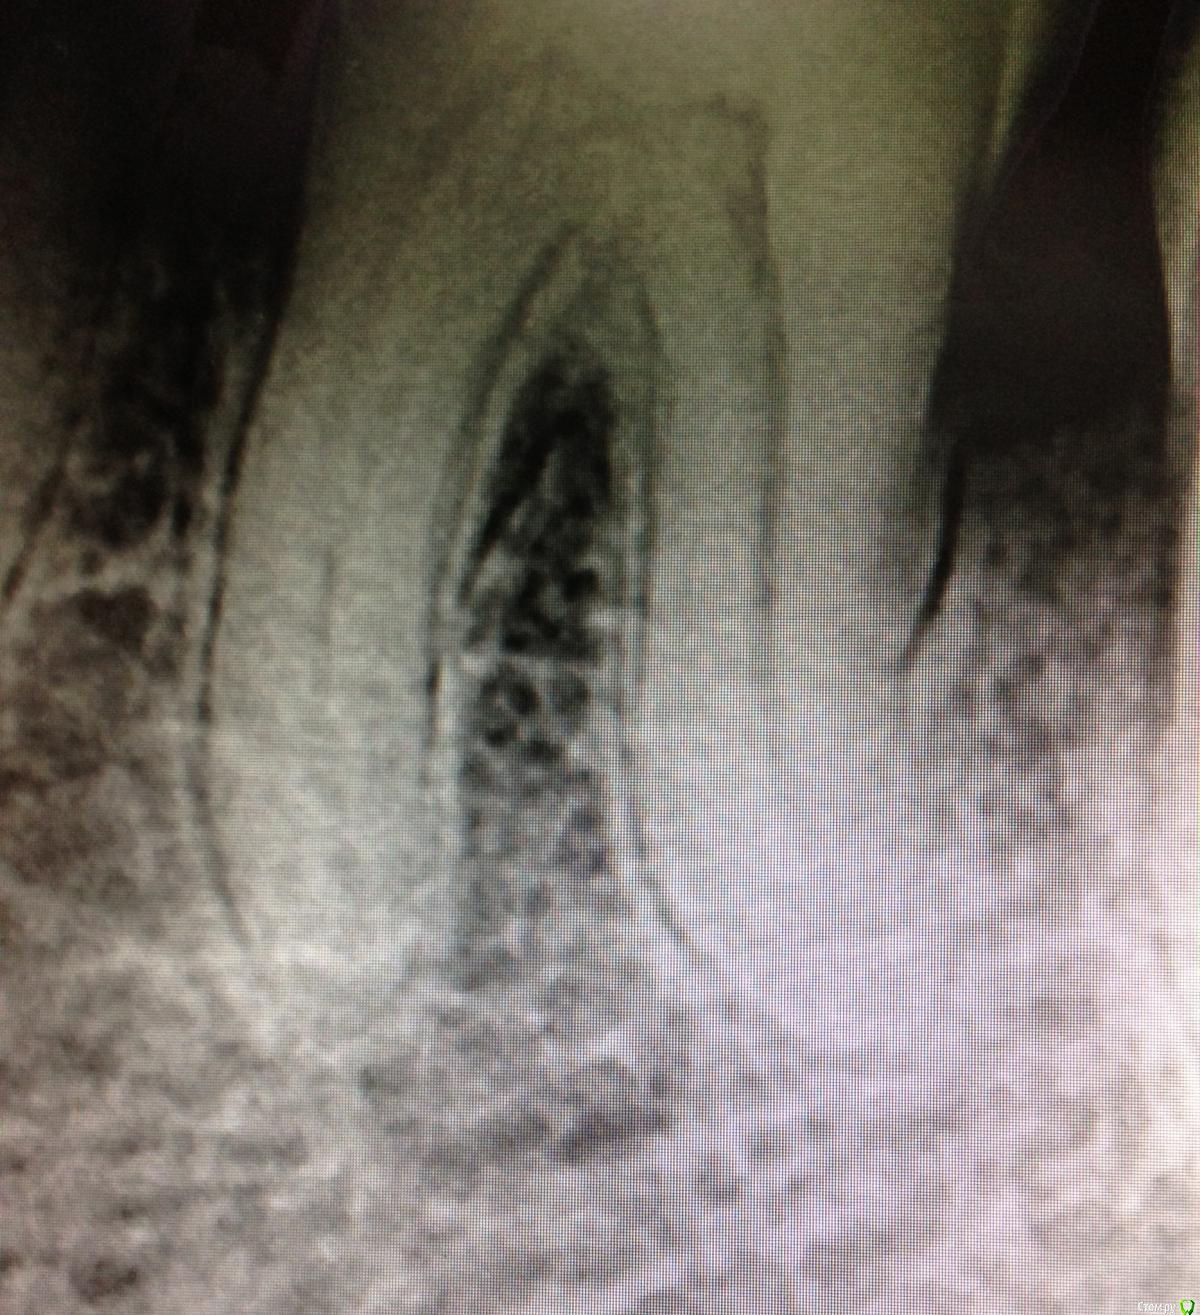

SSTi Опубликовано 9 декабря, 2014 Автор Поделиться Опубликовано 9 декабря, 2014 Чуть обновимся. Пульпитный 36. Медиальные профайлы 35.04. Дистальный 40.04. ОХАП 37. Резорцин старый. Через кальций. 12 хап. 13 пульпит. 60 упор 5 Ссылка на комментарий